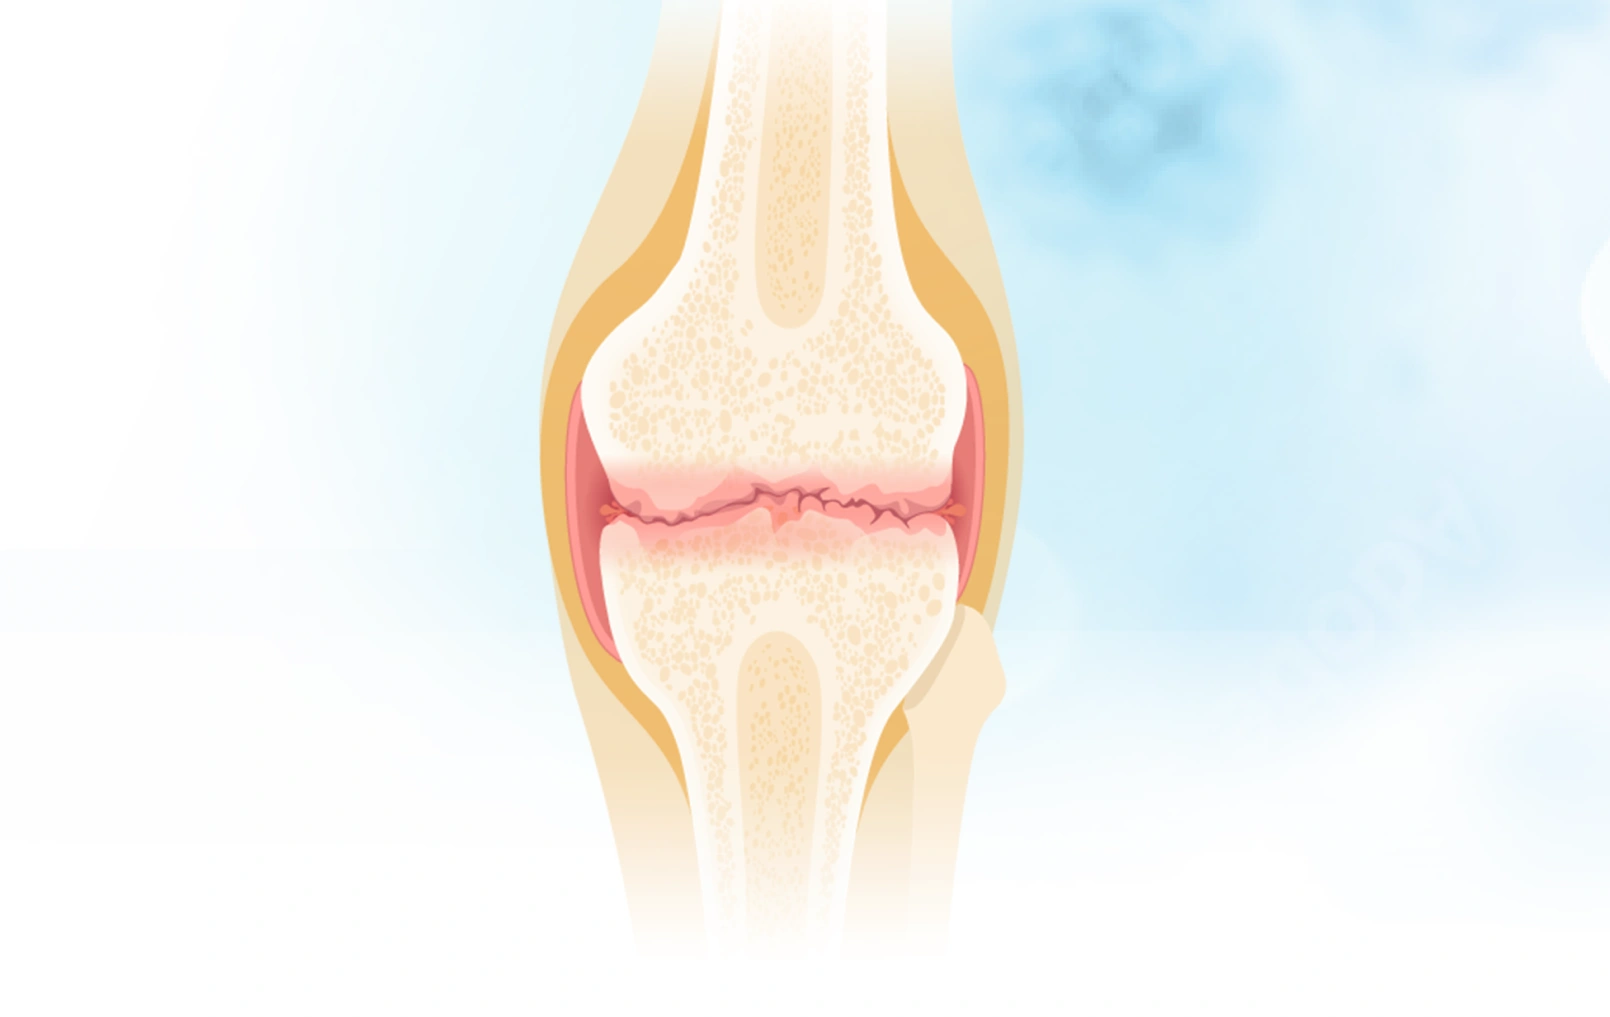

关节里的“减震器”去哪了?深度拆解骨关节炎的本质

骨关节炎的病理生理机制

你有没有想过,为什么有些人50岁就膝盖疼得上不了楼,而有些人80岁还能爬山? 为什么关节里那层看似不起眼的软骨一旦出问题,就能让一个人从"健步如飞"变成"举步...

骨关节炎的疾病概述与定义